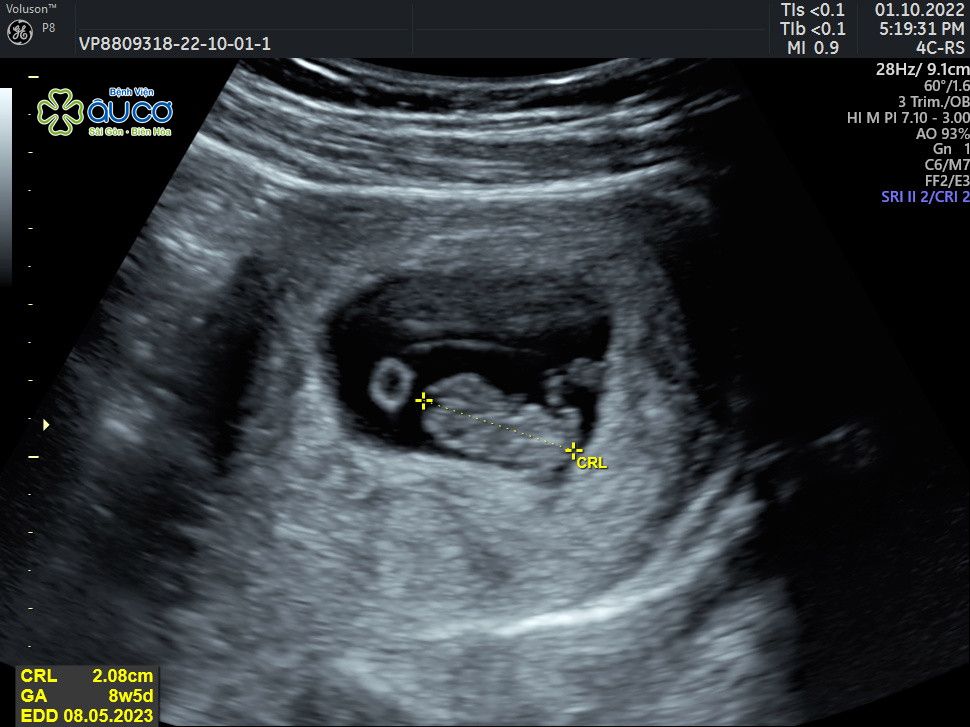

* Những hình ảnh siêu âm đáng yêu nhưng không kém phần nghịch ngợm của con qua các mốc thời gian:

![]() |

| 8 tuần 5 ngày |